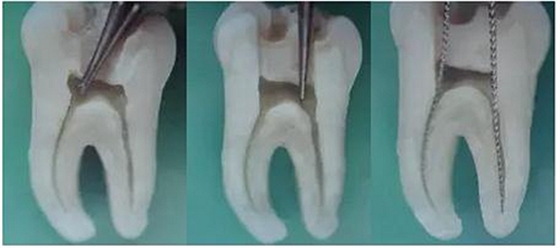

1.開(kāi)髓:洞型是否制備的符合要求,髓室頂是否揭得剛剛好,沒(méi)有破壞洞壁及洞底結(jié)構(gòu)。

圖1裂鉆鉆到近髓 圖2球鉆穿髓 圖3小號(hào)銼探查根管口

圖4 球鉆揭髓頂 圖5修整洞型 圖6完成開(kāi)髓